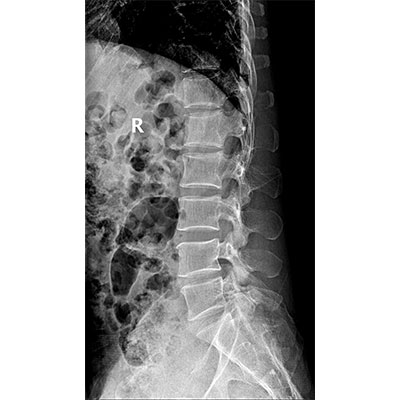

● 采用自主研發(fā)的技術(shù),在保證優(yōu)質(zhì)圖像的前提下,大大降低X射線(xiàn)劑量,用心呵護醫護工作者及患者的健康。

● 短曝光時(shí)間,便于老年人、兒童、殘疾人進(jìn)行臨床拍攝。避免這類(lèi)群體因不能有效控制身體運動(dòng)等因素造成的運動(dòng)偽影,提高攝片質(zhì)量及效率。